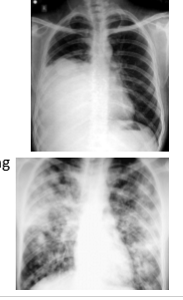

What do u term each of these pics in terms of opacity?

Pic 1: homogenous opacity - area of opacity with UNIFORM DENSITY throughout, appearing evenly white or grey

Pic 2: heterogenous opacity: area of opacity with NON-uniform density, appearing as a mix of lighter and darker regions